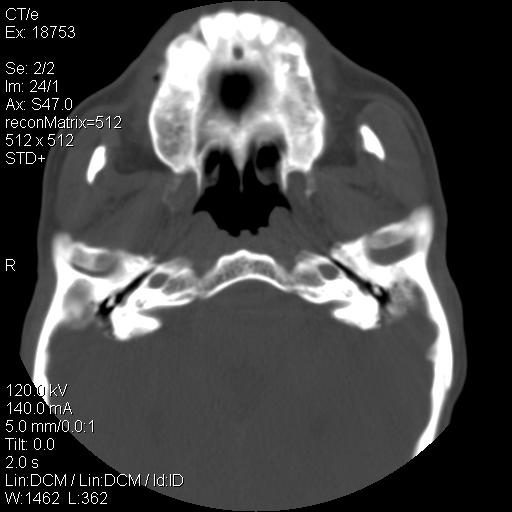

标题: CT21693:男 58岁 右侧咽部疼她2天余 PE:右侧扁桃体肿大 压痛 [打印本页]

标题: CT21693:男 58岁 右侧咽部疼她2天余 PE:右侧扁桃体肿大 压痛

1 弥漫性肿胀,与周围组织分界清晰,发病急,有明显症状,考虑急性炎症【wbc]

弥漫性肿胀,与周围组织分界不清,发病急,有明显症状,考虑:感染性病变!

右化脓性扁桃体炎症伴咽后壁脓肿形成.